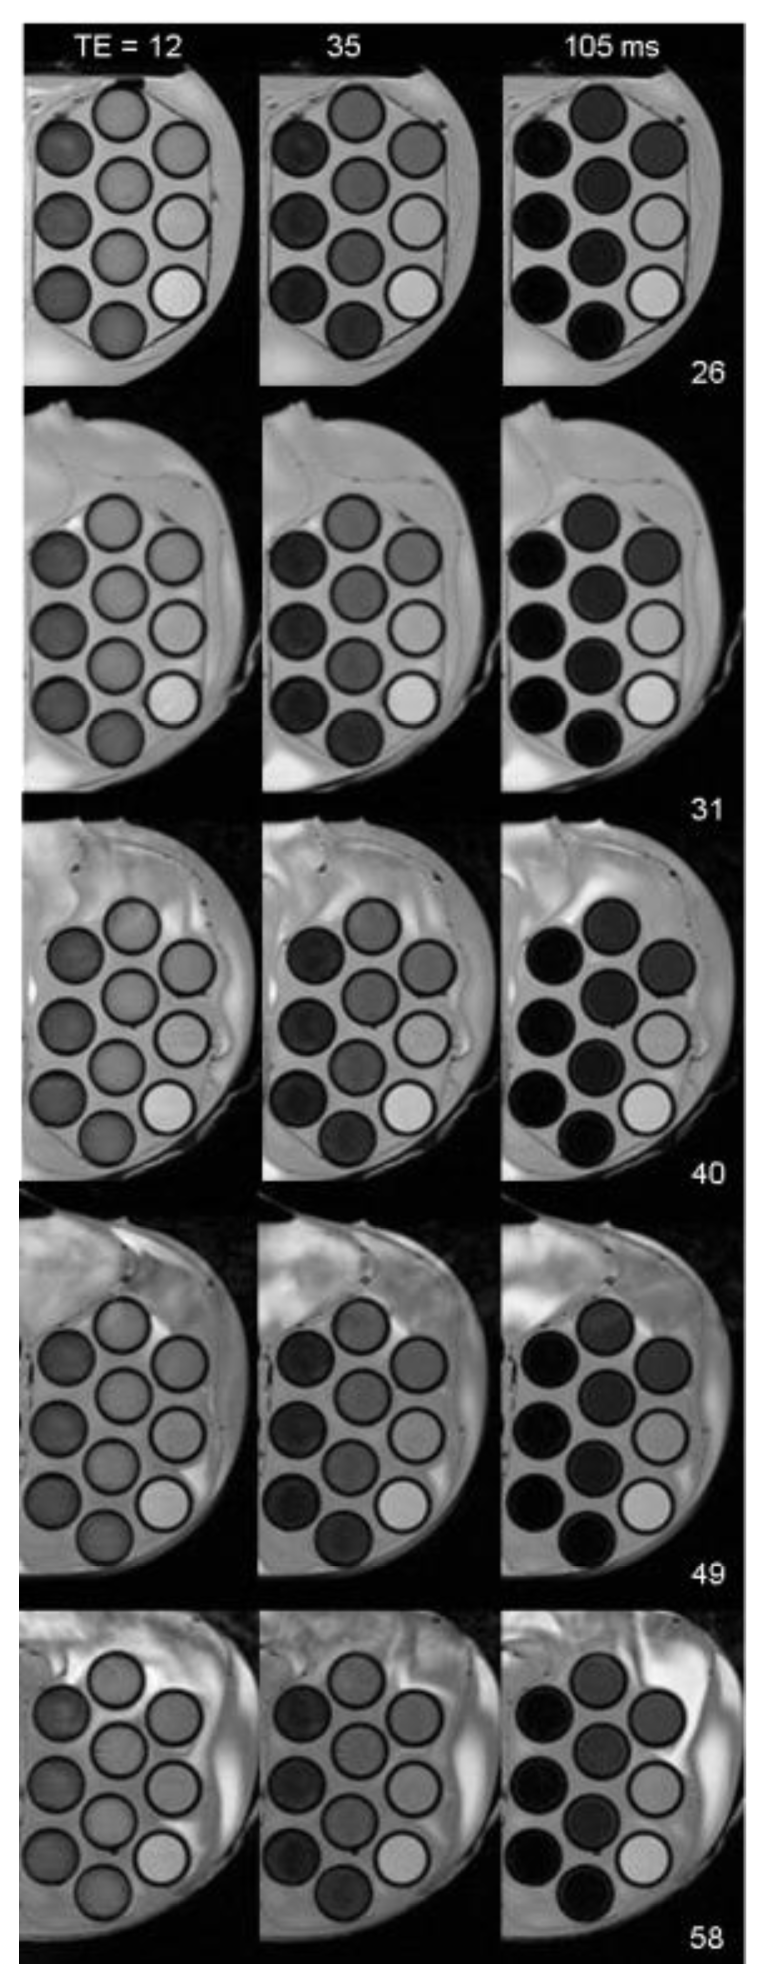

- Issa, B.; Obaidat, I.M.; Hejasee, R.H.; Qadri, S.; Haik, Y. NMR relaxation in systems with magnetic nanoparticles: A temperature study. J. Magn. Reson. Imaging 2013. [Google Scholar] [CrossRef]

- Issa, B.; Qadri, S.; Obaidat, I.M.; Bowtell, R.W.; Haik, Y. PEG coating reduces NMR relaxivity of Mn0.5Zn0.5Gd0.02Fe1.98O4 hyperthermia nanoparticles. J. Magn. Reson. Imaging 2011, 34, 1192–1198. [Google Scholar]